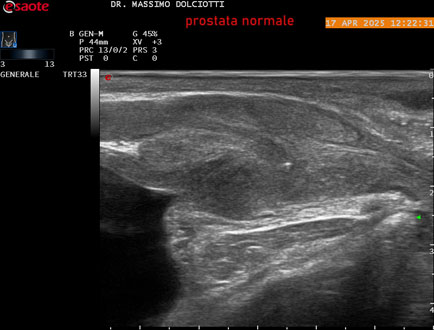

Data inserimento: 01/10/2025

Ecografia del: 17/04/2025

Strumento: Esaote MyLab Eight

Sonda: Convex Multifrequenza 1-8 MHz, Endocavitaria Multifrequenza 3-9 MHz e 3-13 MHz

Età Paziente: M 35 anni

Motivazione dell'esame: disuria.

Commento all'esame: le immagini ed il video documentano la prostata di ecostruttura regolare e morfovolumetria normale con diametro trasversale di 40 mm, diametro anteroposteriore di 21 mm e diametro longitudinale di 43 mm, con volume prostatico calcolato di 18 cc (v.n. < 20 cc), il profilo prostatico è regolare e netto, non si documentano calcificazioni intraghiandolari, la vascolarizzazione della ghiandola è normale. La vescicola seminale destra presenta diametro longitudinale di 44,4 x 7,8 mm, la vescicale seminale sinistra ha diametro longitudinale di 45,3 mm x 7,2 mm.

Conclusioni: prostata normale (normal prostate).